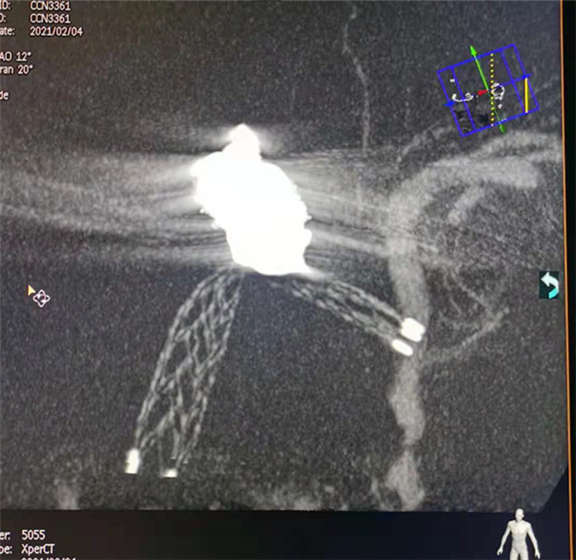

颅内动脉瘤支架辅助下介入栓塞术,支架植入后,术中即刻可以通过支架显影技术清晰支架的展开及血管贴壁情况,准确评估手术效果

该血管造影机能够明显提高图像质量,对于复杂畸形和较小的腔内器材(如颅内血管微支架等)的显示更具优势。使医生在血管造影及介入手术中可以看到更多的临床影像细节,使微血管和细小病灶得以更加清晰的显示,同时又兼容心脏与外周介入的综合需求,还兼具增强CT功能,可以进行三期扫描,清晰显示病变和微细血管。